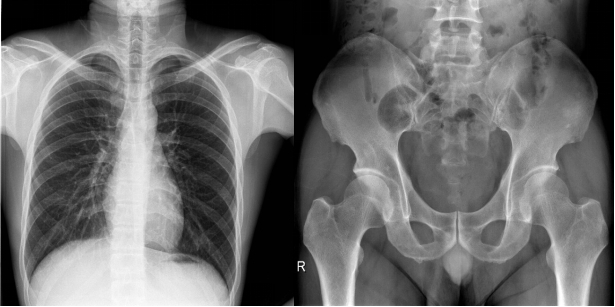

【固定悬吊dr-PLD7800E部分临床效果图】